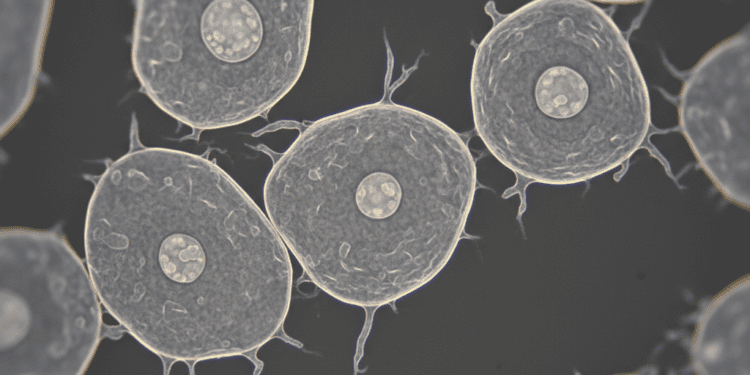

O principal diferencial da microscopia confocal é seu uso do mencionado corte óptico laser. Um feixe de laser é utilizado para iluminar apenas uma parte da amostra em um dado instante. Isso, combinado com um sistema de pinhole que bloqueia a luz indesejada de outros planos, resulta em imagens muito nítidas. Essa técnica é particularmente útil para visualizar estruturas celulares complexas e pode ser aplicada a diversas amostras, incluindo células orais.

O estudo das células orais, como os queratinócitos, fibroblastos e células imunes, é fundamental para compreender várias condições de saúde bucal. Os cortes ópticos gerados pela microscopia confocal permitem que os cientistas investiguem a morfologia, organização e comportamento dessas células de maneira detalhada.